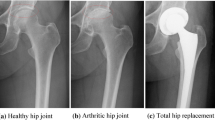

When natural joints fail due to trauma, disease, or overuse, replacement with artificial ones is needed to maintain the joint function and relieve the pain of patients. Joint replacement, also called joint arthroplasty, is a surgery that removes parts of an arthritic or damaged joint and replaces it with artificial implants or prosthesis comprised of metal, plastic, or ceramic devices. Prosthesis is designed to replicate the movement function of a normal and healthy joint. Nowadays, roughly 570,000 primary total hip and knee replacements are performed in the United States each year [1, 2]. According to the American Academy of Orthopedic Surgeons, the procedures performed in the United States are expected to increase to at least 750,000 per year by 2030 (Fig. 1.1) [3].

Despite the long-lasting demands for artificial joints, it has taken about two centuries for human beings to establish the modern joint implant designs as well as optimal materials for joint implants. The earliest attempt of hip replacement occurred in 1891. Gluck presented the first use of ivory to replace femoral heads for a patient whose hip joints had been destroyed [4]. Since then, worldwide, surgeons carried out the interpositional arthroplasty from the late nineteenth to early twentieth century, which involved placing a variety of tissues between articulating surfaces of a remodeled joint, such as the fascia lata, skin, and pig bladder submucosa [5]. The first mold arthroplasty out of glass was performed by an American surgeon Marius Smith-Petersen in 1925. This mold consisted of a hollow hemisphere that can fit the femoral head and give rise to a new smooth surface required by the joint movement. However, the glass failed to endure great forces through the hip joint during movements. A British surgeon, George McKee, was the first to use a metal-on-metal prosthesis on a regular basis in 1953. He used the modified Thompson stem, which was a cemented hemiarthroplasty used for the neck of femur fracture. That implant showed a 28-year survival rate of 74% [6]. Unfortunately, that prosthesis was more and more unpopular in the 1970s because the local effect of metal particles was found during the revision surgery for prosthetic failures [7]. An orthopedic surgeon, Sir John Charnley, proposed low-friction arthroplasty in the early 1960s and thus created an era of modern total joint arthroplasty. This design is still used today as a golden standard. It is comprised of three parts: (1) a metal femoral stem, (2) a polyethylene acetabular component, and (3) an acrylic bone cement. Thus, a small femoral head is used to reduce wear due to its small surface area [8, 9].